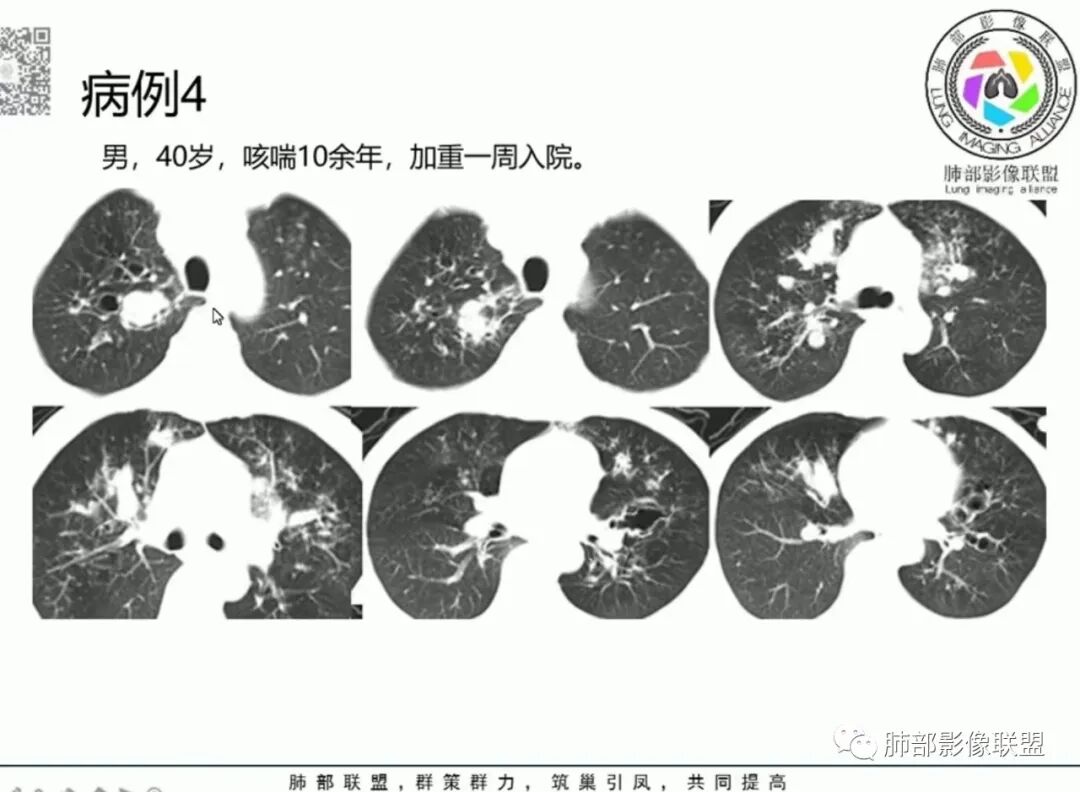

【每日晨读】又见ABPA!

变应性支气管肺曲霉病 (allergie bronchopulmonary as-pergillosis,ABPA)是烟曲霉致敏引起的一种变应性肺部疾病,表现为慢性哮喘和反复出现的肺部阴影,可伴有支气管扩张。该病相对少见,临床上常被误诊为支气管哮喘(以下简称哮喘)、支气管扩张等;而早期诊断、及时给予全身糖皮质激素(以下简称激素)治疗,可控制病情,防止不可逆性肺部损害的发生。

胸部影像学的特异性改变:随着胸部高分辨率CT(HRCT)的普及,ABPA常见肺部影像表现包括黏液嵌塞、支气管扩张、小叶中心性结节、树芽征和马赛克征等。根据是否有中心性支气管扩张,ABPA可分为变态反应性支气管肺曲霉病-血清IgE增高型(ABPA-S)和变态反应性支气管肺曲霉病-中心性支气管扩张型(ABPA-CB)。气道黏液嵌塞在ABPA很常见,胸部HRCT上表现为指套征或牙膏征。气道黏液栓通常为低密度影,但20%也可为高密度黏液影(high-attenuation mucus,HAM),定义为气道内黏液栓密度高于脊柱旁肌肉的 HRCT值,这也成为ABPA特征性的影像表现之一,外周细支气管黏液阻塞可见“树芽征”。中央性支气管扩张曾一直是ABPA诊断标准之一,但其用于诊断ABPA的敏感度仅为37%。此外,33%~43%的中央性支气管扩张也可延伸至外周,26%~39%的ABPA只有周围性支气管扩张。因此,目前认为中央性支气管扩张应视为ABPA的并发症,而非其诊断标准。